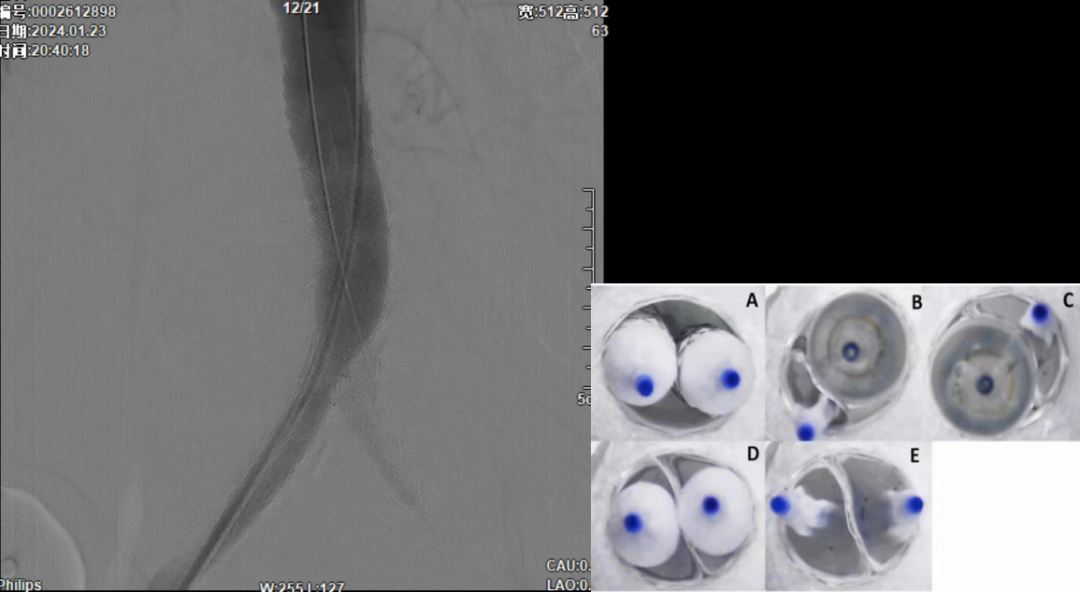

在超声引导下,成功完成双侧股总动脉穿刺。通过导管配合超滑导丝,顺利通过病变区域进入腹主动脉下段,造影明确腹主动脉下段及双侧髂动脉完全闭塞的病变范围与程度。

采用8F Rotarex导管对双侧髂动脉及腹主动脉下段进行减容处理。该器械对于陈旧性血栓具有良好的清除效果,且适用于支架内病变的治疗。减容治疗的主要目的在于获得理想的管腔空间,同时降低远端动脉栓塞的风险。

减容后造影显示仍存在重度残存狭窄,遂沿右侧股动脉置入VBX支架(直径11mm,长度59mm)。支架定位需满足近端完全覆盖腹主动脉病变段,远端距离双侧髂总动脉分叉至少1.5cm,以避免后扩张时大球囊对髂动脉造成损伤。

该图解释为何远端距离双侧髂总动脉分叉至少1.5cm,以避免后扩张时大球囊对髂动脉造成损伤。

CERAB技术的关键点一:经双侧股总动脉植入2枚VBX球囊扩张式覆膜支架(8L×79mm),与腹主动脉覆膜支架腔内平行放置,且两枚支架端平齐对接。